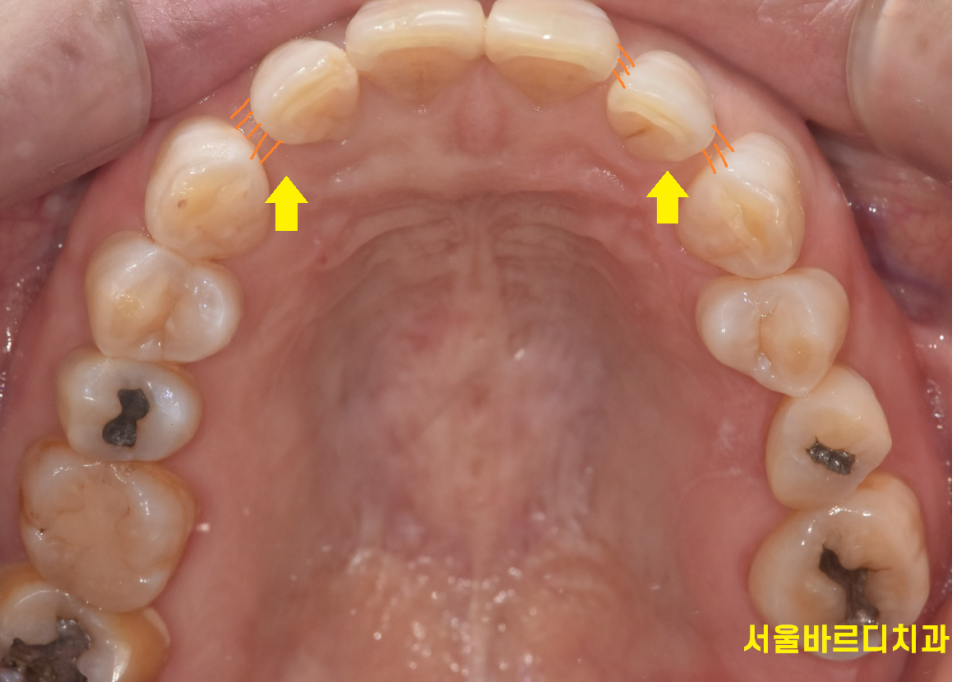

241209

앞니 사이 틈이 없어졌죠~?

공간이 메워지면서 음식물이 끼는 등의 불편함도 사라지시겠어요.

아래 치아가 없는 부분은 임플란트 치료중이신데

앞니만 교정하기 때문에 임플란트 치료중에도 받으실 수 있습니다!